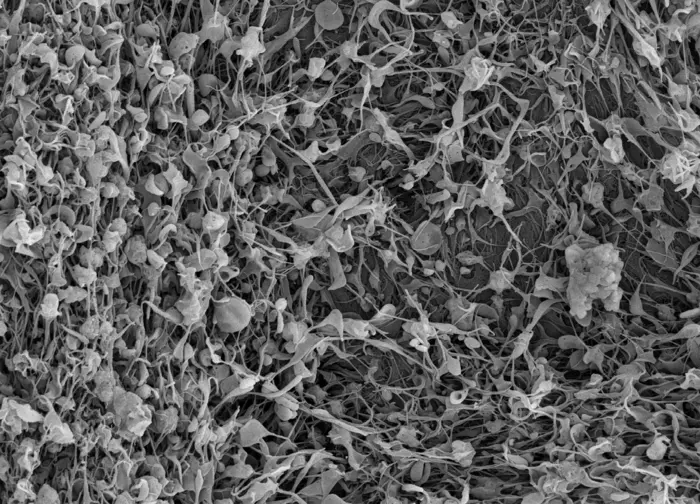

Working to address that, the Sen Gupta lab at Case Western Reserve has developed a technology that can mimic the platelet's ability to facilitate the generation of fibrin.

Simultaneously, the Brown lab at UNC/NCSU has developed a technology that mimics the biomechanical property of platelets to bind to fibrin and stabilize the clot by changing shape.

The new DoD grant will allow the researchers to integrate these capabilities into a single injectable nanotechnology for the combined effect of fibrin formation and stabilization. Studies at CWRU and UNC/NCSU will help evaluate and optimize the integrated technology. It will then be tested in a traumatic injury model at Pitt to establish its ability to stop hemorrhage and improve survival.